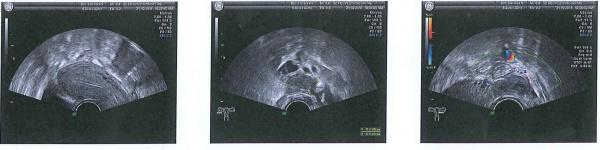

图一,第一次做B超是10月13日做的阴超,刚排完卵,图片是B超单上扫描下来的,可能不是很清楚。

右附件区见一无声区大小,大小约29*18mm,边界清晰,呈类圆形,内部透声一般,可见密集点状弱回声漂浮其中,后方回声增强,CDFI:右侧附件区异常团块周边可见血流信号。

左侧卵巢内可见大小约22*17mm的异常回声团,边界清晰,呈类圆形,内部可见无回声,并可见一15*12mm稍强回声团,后方回声增强,CDFI:左侧附件区异常团块周边可见血流信号。

1、右附件区考虑巧克力囊肿,

2、左侧卵巢内囊实

性病变,性质待定。

图二,是月经结束后第三天做的阴超,

右侧卵巢内可见大小约29*16mm的异常回声,形状呈椭圆形,内部为低回声,内可见密集细小光点回声,挤压后,光点移动不明显,壁厚不光滑,边界清楚,后壁回声增强,CDFI:包块包膜上未见明显血流信号。

左侧卵巢内可见一个大小约22*16的混合回声区,边界清楚,呈椭圆形,内部可见大小约6*5mm的强回声,内部并可见无回声及低回声区,CDFI:异常周边可见少量血流信号,其内未见明显血流信号,

陶氏腔内可见液性暗区,最大前后约9mm

右侧卵巢考虑巧克力囊肿可能,

左侧卵巢内混合性包块,性质待定

陶氏腔少许积液